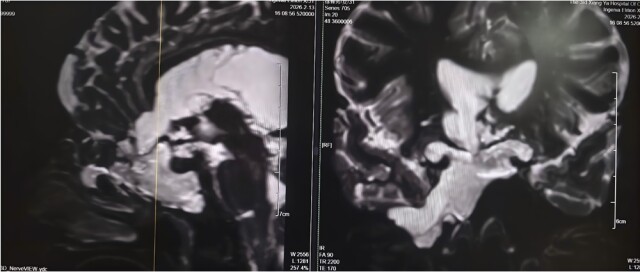

4年前,刘女士开始出现鼻腔流血、反复清水样流液,并伴有嗅觉减退。期间,她曾辗转多家医院及诊所就诊,医护人员多以“炎症”为病症进行对症治疗,但症状始终未得到根本改善。此后,刘女士多次出现发热伴鼻腔流液的情况,却一直未能明确病因,病情反复迁延。今年2月11日,刘女士病情突然恶化,突发高热,体温超过39℃,并出现神志模糊的症状。当地医院紧急诊断后,确诊其为“脑脊液鼻漏合并颅内感染”,并下达了病危通知。危急时刻,家属紧急将刘女士转送至湘雅三医院功能神经外科求治,寻求进一步救治。 刘女士入院后,该院功能神经外科杨靓副主任医师团队第一时间为其完善影像及实验室检查。经系统评估与综合分析,专家团队明确诊断刘女士所患疾病为——与脑室相通的高流量脑脊液漏,且其颅内感染情况较为严重。

团队指出,此类高流量脑脊液漏病情复杂,治疗难度极高:若直接进行修补手术,术后极易因颅内压力过高导致修补失败;同时,若在感染未充分控制前贸然封堵漏口,可能因失去引流通道导致颅内压骤升,进而造成病情急剧恶化,甚至危及患者生命。为确保治疗安全有效,经多学科讨论后,杨靓团队为刘女士量身制定了“先引流控制感染,后精准修补漏口”的阶梯式治疗方案,分阶段推进救治工作,最大限度降低治疗风险。

2月14日,杨靓团队为刘女士实施“脑室—腹壁外引流术”,通过手术将其颅内感染的脑脊液引流至体外,同时联合规范的抗生素治疗,双管齐下控制感染。据悉,脑室—腹壁外引流术是一种临时的微创脑脊液引流手术,可快速降低颅内压力、廓清感染脑脊液,为后续根治性手术创造条件。经过持续引流和脑脊液更新,刘女士的感染症状迅速得到控制,体温逐渐恢复正常,意识也逐步清醒,病情趋于平稳。2月26日,在确认刘女士颅内感染完全控制、身体条件达到手术标准后,杨靓团队为其开展经鼻内镜脑脊液漏修补术。术中,专家团队借助高清内镜的精准视野,准确定位漏口位置,同时从刘女士大腿取少量自体组织,为其完成多层严密修补,实现精准“堵漏”。据了解,经鼻内镜脑脊液漏修补术具有创伤小、恢复快、并发症少的优势,已成为脑脊液鼻漏修补的优选方式之一。术后第一天,刘女士鼻腔清水样流液的症状便完全消失,困扰其多年的头痛也明显缓解。经过后续规范的护理与康复治疗,刘女士身体恢复良好,于3月初顺利出院,彻底摆脱了困扰4年的病痛。